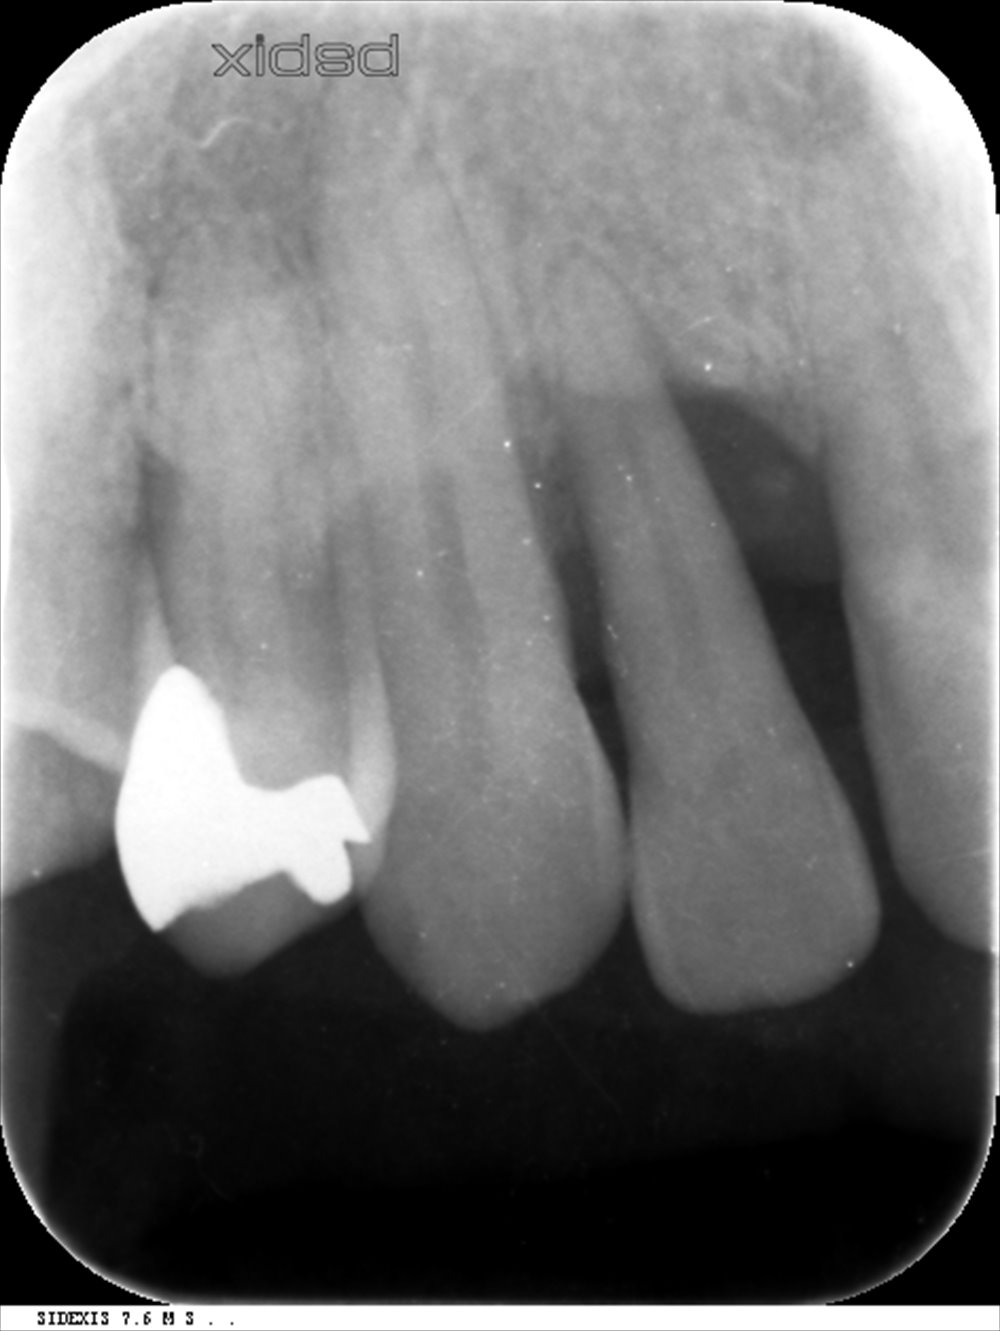

MINST処置後6ヶ月

歯槽骨が明瞭になり安定しています。骨様の再生もありポケットは3mm以下です。